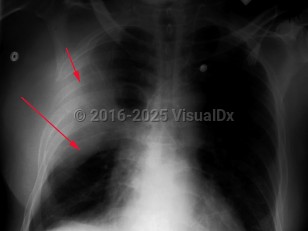

Klebsiella pneumonia

Klebsiella pneumonia is caused by Klebsiella pneumoniae, an enteric gram-negative rod. Klebsiella pneumoniae usually enters the lung via aspiration of oral secretions and can result in both community-acquired pneumonia as well as hospital-acquired pneumonia. Most cases occur in the hospital.

The onset of symptoms is sudden with pleuritic chest pain, chills, prostration, moderate fever, dyspnea, and productive cough. The sputum can be thick and bloody, greenish, and also have a "currant jelly" appearance. The white blood cell count is usually elevated, but neutropenia appears to be frequent in those with cirrhosis and Klebsiella infection. Bacteremia can occur in up to 25% of cases. Complications can include lung abscesses, pericarditis, empyema, and meningitis. Rarely, there can be eye complications. In hypervirulent cases, pyogenic abscesses can form in the liver, central nervous system, urinary tract, soft tissues, and other sites.